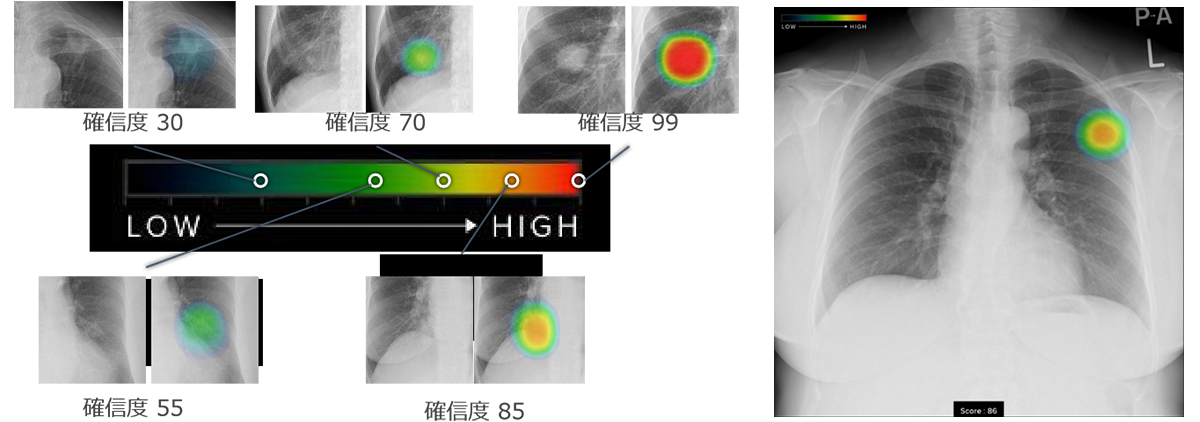

胸部レントゲン検査